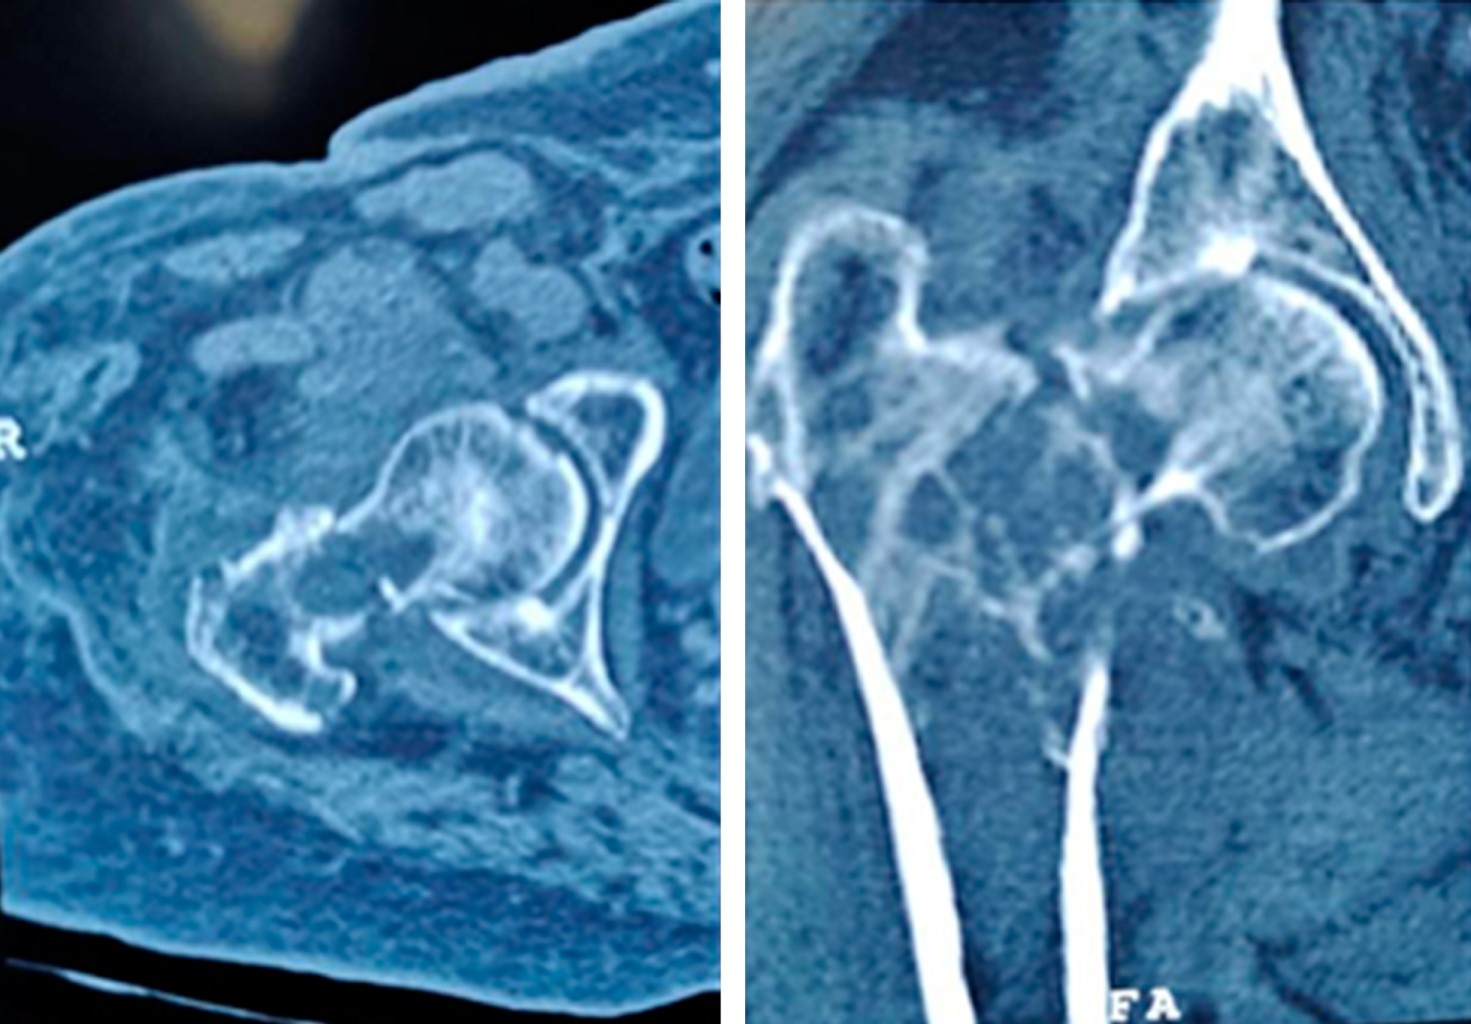

Bone metastases from a primary cancer of any part of the body are the most common form of malignant bone tumor constituting approximately 70% of them. The proximal femur being the most common extra-vertebral location for its location; 10% of patients have some pathological fracture, which is a serious complication. Currently the objectives of the treatment of a pathological fracture are: resection with adequate oncological margins, that the patient survives the surgical intervention, maintain the functionality, that the placed implant has a longer life time than the patient. The use of non-conventional hip prostheses is an excellent treatment option fulfilling the 4 established objectives, therefore this case is presented in which a right bipolar hip hemiarthroplasty is performed with a non-conventional prosthesis where it was treated with a described complication and the surgery of resolution.

Figure 1